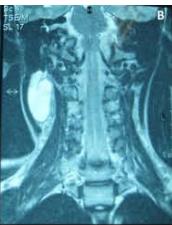

Figure/Patient 3

An 8 year-old girl with prior surgical excision of a right latero-cervical lymphangioma presenting with a new-onset tumefaction within the same region. MRI scans show a 9-10 cm subcutaneous multilocular lesion, extending between two virtual planes crossing the retro-molar trigone and the thyroid respectively, with deep invasion of parapharyngeal spaces cranially and the space between the submandibular gland and the vascular peduncle of the neck caudally. The lesion appears hyper-intense on T2 weighted scans with (A-B) and without (C-D) fat suppression, hypo-intense on T1 weighted scans with (E) and without (F) fat suppression and hyper-intense on DWI scans with high B values (G). Diagnosis of loco-regional recurrence of cystic lymphangioma is done.